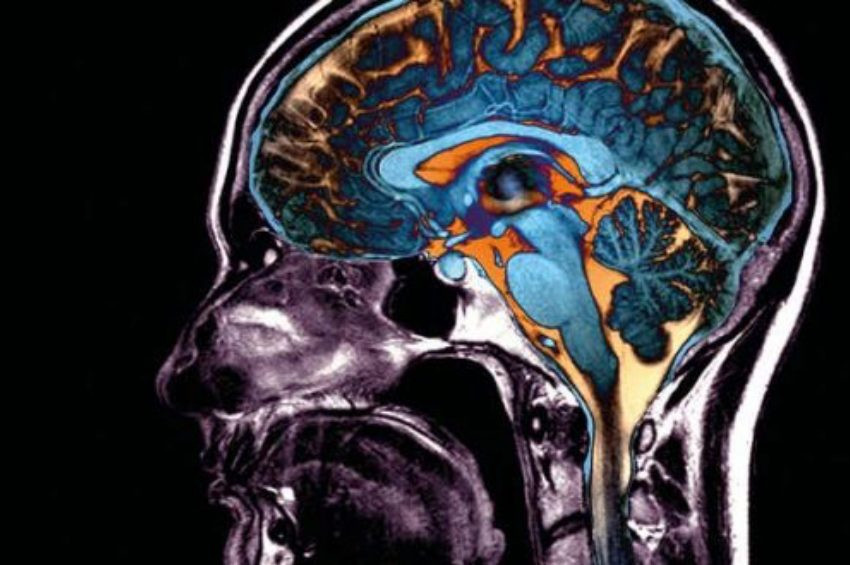

Normalde hastalığın akciğerlere saldırdığı bilinirken, beyne sıçraması pek beklenen bir şey değil. Yeni koronavirüsün nasıl bu türde semptomlar yarattığı ise büyük bir soru işareti. Giderek artan kanıtlar, virüsün nöronlara doğrudan saldırabileceğini gösteriyor. Eğer virüs beyne saldırıyorsa, uygulanan tedavilerin de yeninden gözden geçirilmesi gerekiyor. Ayrıca Covid-19 geçiren hastalarda uzun süreli ve kronik nörolojik durumların da oluşabileceğine kendimiz hazırlamalıyız.

Bununla beraber hastalarda ayrıca baş ağrıları ve baş dönmesi gibi nörolojik semptomlar da görülüyor. Bazı hastalarda daha da ciddi seyredebiliyor; nöbet ve inme görülebiliyor. Bu semptomlar bu koşulları sağlamayan genç insanlar da bile görülmeye başladı. Bazı sonuçlar çok nadir olduğunda halen kesin rakamlar yok. Çin’deki 214 Covid-19 hastasının % 6’sında beyine giden kan akışını etkileyen ciddi bir durum yarattığı görüldü. “Beyinde inmeler ve kanamalar gözlemledik,” diyor Frontera, Brooklyn NYU Langone Hastanesi’nden. Ayrıca Covid-19 hastalarında beyin enflamasyonu ve beyin hasarına dair elle tutulur ciddi vakalar rapor edildi.

Araştırmacılar fareleri SARS virüsüyle burundan enfekte ettiğinde, virüsü hayvanların beyin sapında gözlemledi. Beyin sapı, beyin ile spinal kord arasında bulunur ve nefes almayı düzenler. “İşte bu durumda hastaların solunumu hasarının daha da kötüleşebileceğini hayal edebilirsiniz,”diyor Northwestern Üniversitesi Feinberg Tıp Fakültesi’nden Igor Koralnik.

Peki ya yeni koronavirüs ne durumda? Birkaç raporda, covid-19 hastalarının serebrospinal(omurilik) sıvısında koronavirüs tespit edildiği iddia ediliyor.

Ayrıda diğer bir olasılıkta oksijen yetersizliğinden kaynaklı nörolojik semptomların oluşmasıdır. Covid-19’dan ölen hataların büyük çoğunluğunda akciğer hasarı mevcut. Hava keselerinin yüzeyleri kalınlaştığından, oksijenin kana karışmasını zorlaştırıyor, diyor Cleveland Klinik’ten Sanjay Mukhopadhyay.

İşte bu nedenle, mekanik ventilatörle tedavi edilen Covid-19 hastalarının beyin taramalarında hasarlar çıkıyor olabilir. Bu beyin hasarları beynin oksijensiz kalmasından kaynaklanabilir.

Yine de bugüne kadar elde ettiğimiz kanıtlara dayanarak, virüsün beyne girdiğini varsayabiliriz, diyor Nath. Eğer bu doğruysa, virüsün beyne nasıl saldırdığını öğrenmek hayati hale geliyor. “Hastaları tedavi yöntemimiz büyük ölçüde değişecektir,” Nath.

Covid-19 tedavisi için geliştirilen ilaçlar akciğerleri tedavi etmeye odaklanıyor. İlaçları beyne sokmak ise tümüyle başka bir mücadeleye dönüşecek. Beyindeki koruyucu tabaka, kan-beyin bariyeri nedeniyle çoğu ilaç beyne nüfuz edemez.”Bu nedenle tümüyle farklı bir tedavi yaklaşımı gerekecektir,” diyor Nath.